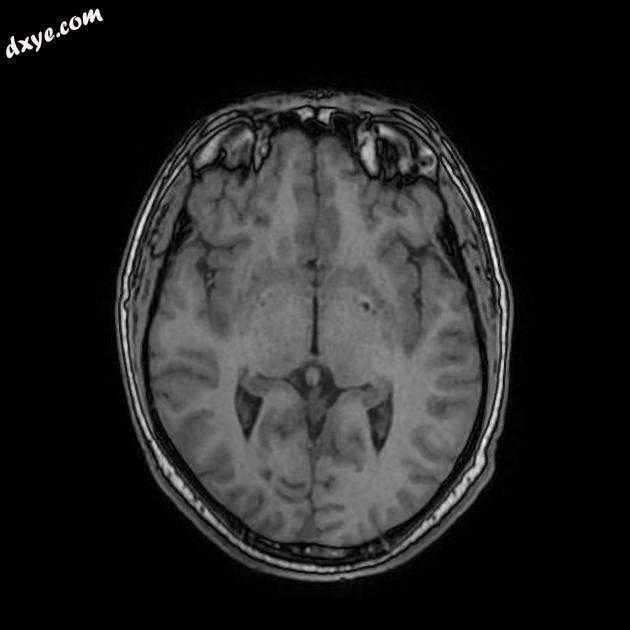

MRI

Axial T1

MRI 序列显示右侧颈内动脉的部分血栓囊状动脉瘤位于 C6/7 节段的交界处,大小为 11 x 7 毫米,颈部为 2.5 毫米,压迫动眼神经 (III) 的相邻节段,在 T1 上清晰可见和 FIESTA 序列。

位于 C6/7 交界处的右侧颈内动脉部分血栓囊状动脉瘤的 MRI 特征,压迫同侧动眼神经 (III)。